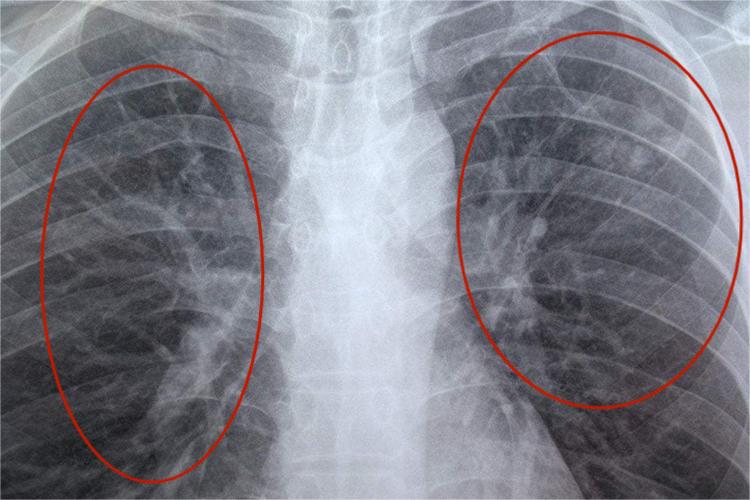

双肺纹理增多紊乱通常出现在胸片或CT等影像学报告中,正常情况下,肺纹理清晰,分布均匀。当肺纹理增多、紊乱时,可能意味着这些结构出现了某种程度的病变或异常。具体来说,可能是由于气管增粗、血管增粗、黏膜增粗等原因导致的。双肺纹理增多紊乱的严重程度需要根据具体病因来判断。以下是一些可能的原因及其对应的严重程度:

双肺纹理增多紊乱是一个相对常见的影像学表现,其严重程度需要根据具体病因来判断。在出现这一表现时,建议患者及时就医,进行进一步的检查和治疗。保持良好的生活习惯和饮食习惯也是预防肺部疾病的重要措施。